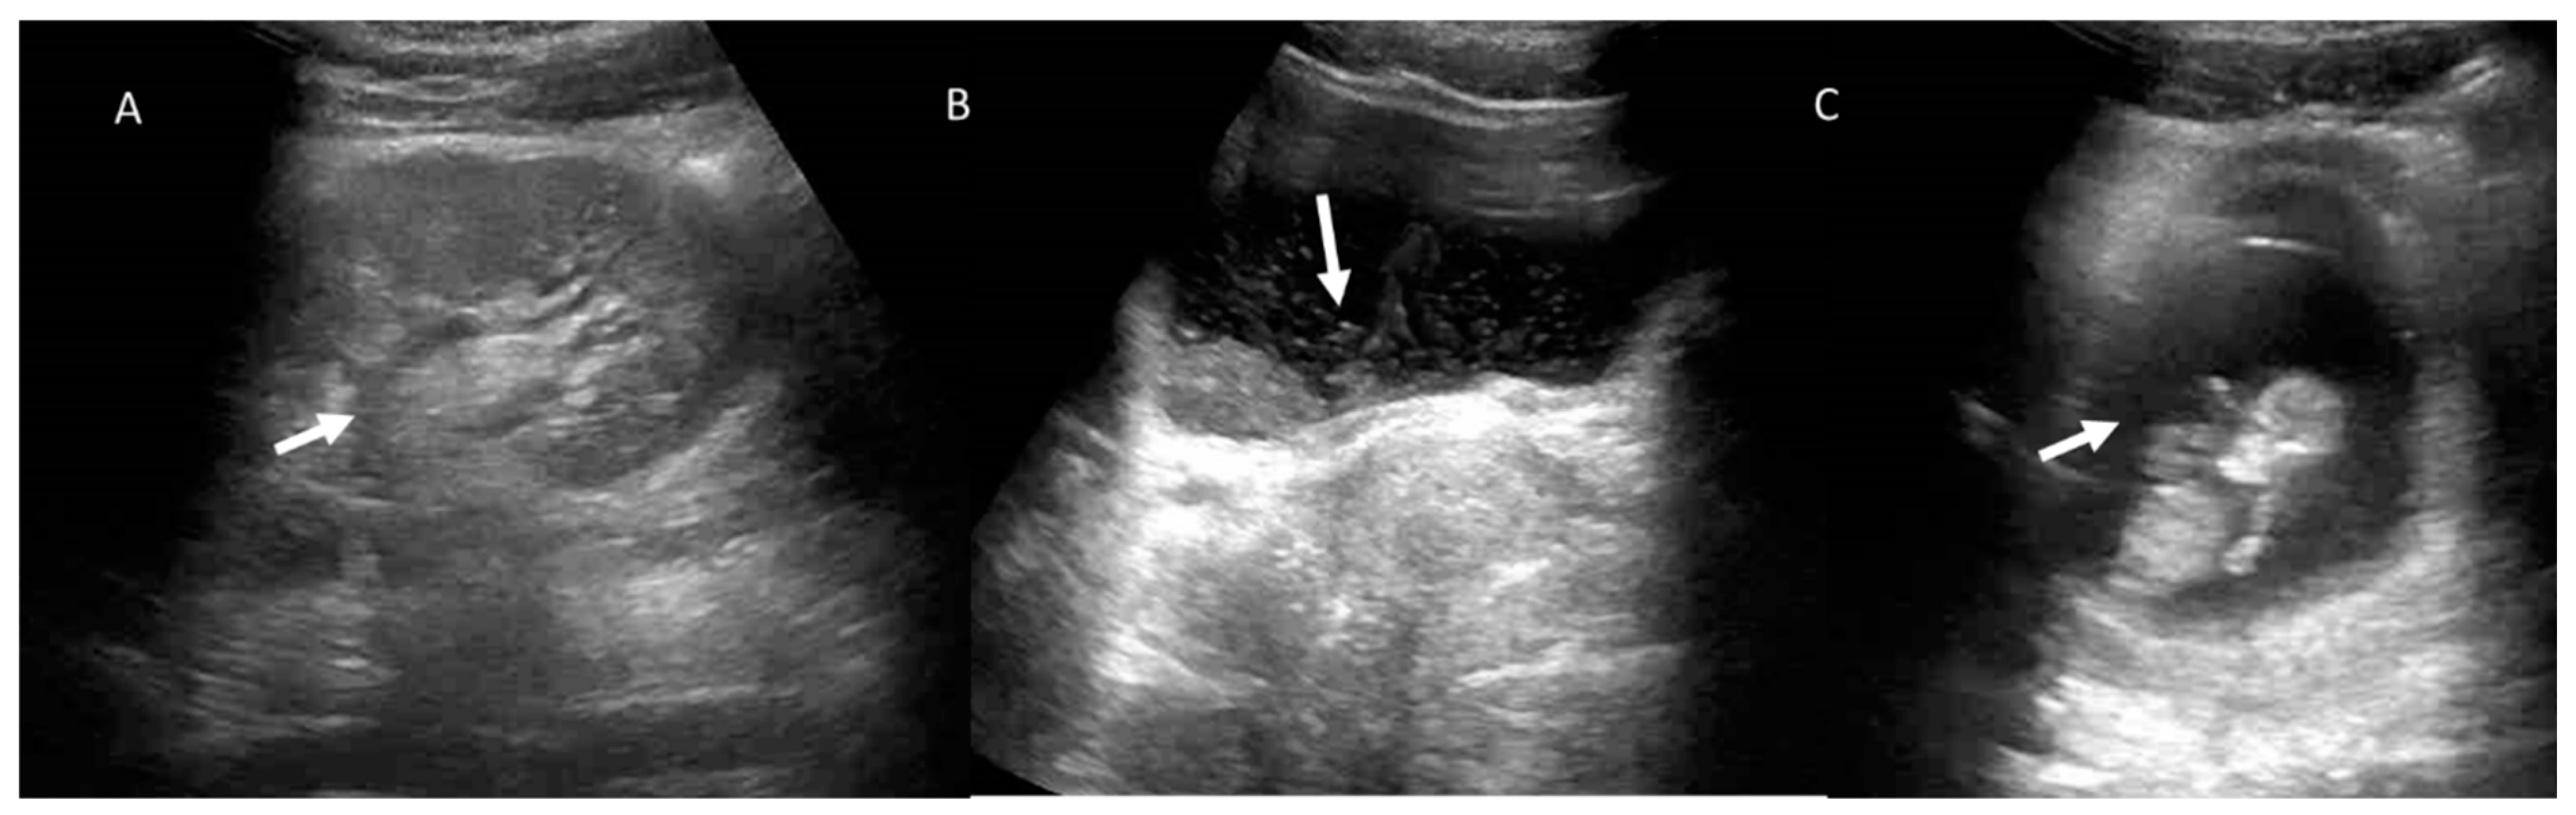

7. Ureterolithiasis

8. Evaluation of the Pregnant Patient with Dyspnoea